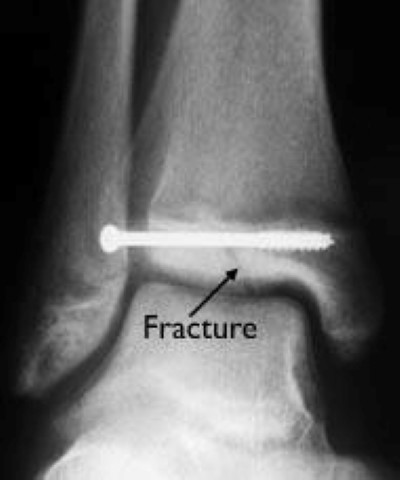

Tillaux fracture surgical fixation

During surgery to treat this Tillaux fracture, the bone fragments have been set into alignment and held together with a screw fixation.

Image courtesy of Stuart J. Fischer, MD, FAAOS